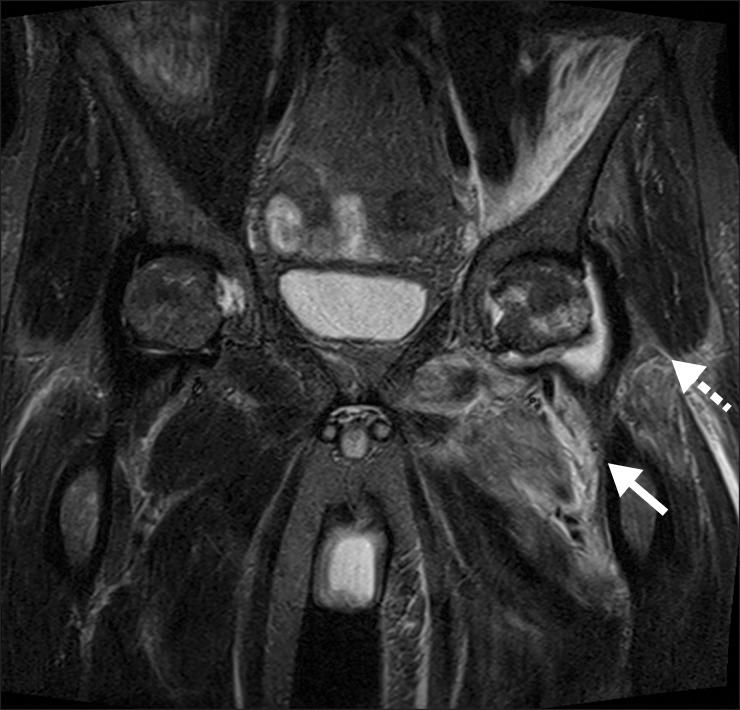

Non-typhoid salmonellosis is an infectious disease caused by Salmonella species other than Salmonella typhi. Although the usual clinical course of non-typhoid salmonellosis is a benign self-limiting gastroenteritis, these bacteria are especially problematic in immunocompromised individuals, including patients with malignancies, human immunodeficiency virus, or diabetes, and those receiving corticosteroids or other immunotherapy agents. In addition to enteric symptoms, Salmonella species give rise to extra-intestinal complications, including self-limiting arthritis, which appears 1 to 3 weeks after the onset of infection and lasts from a few weeks to several months. In some patients, however, this arthritis spears to be chronic in nature. We describe herein a living-donor liver transplant recipient who experienced non-typhoid Salmonella-triggered arthritis in the left hip. The patient recovered uneventfully after 6-month-long antibiotics treatment. Clinicians involved in transplantation should be aware of the possibility that transplant recipients, like other immunocompromised individuals, are at risk of salmonellosis and therefore require careful clinical and microbiological evaluation, with the goals of prevention and early recognition of infection.

非伤寒沙门氏菌病是由伤寒沙门氏菌以外的沙门氏菌属引起的一种传染病。虽然非伤寒沙门氏菌病的通常临床病程是良性自限性胃肠炎,但这些细菌在免疫功能低下的个体中尤其成问题,包括患有恶性肿瘤、人类免疫缺陷病毒或糖尿病的患者,以及接受皮质类固醇或其他免疫治疗药物的患者。除肠道症状外,沙门氏菌属还会引发肠外并发症,包括自限性关节炎,这种关节炎在感染发作后1至3周出现,持续数周至数月。然而,在一些患者中,这种关节炎似乎本质上是慢性的。我们在此描述了一名活体供肝移植受者,他在左髋部出现了非伤寒沙门氏菌引发的关节炎。经过6个月的抗生素治疗,患者顺利康复。参与移植的临床医生应意识到,移植受者与其他免疫功能低下的个体一样,有感染沙门氏菌病的风险,因此需要进行仔细的临床和微生物学评估,以预防和早期识别感染。